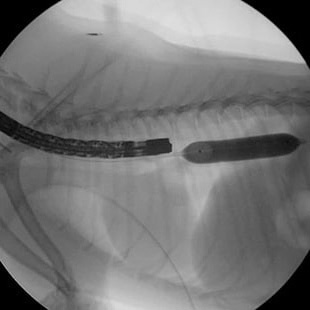

· 기관 스텐트 장착 전

· 기관 스텐트 장착 후